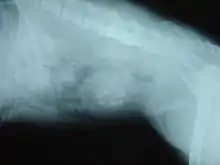

When symptoms indicate bladder stones, the first step is usually to take an x-ray. Most types of stones will appear readily in an x-ray, urate and occasionally cystine stones being the most common exceptions. Stones smaller than three millimeters may not be visible.[4] Ultrasonography is also useful for identifying bladder stones. Crystals identified in a urinalysis may help identify the stones, but analysis of the stones is necessary for identification of the complete chemical composition.